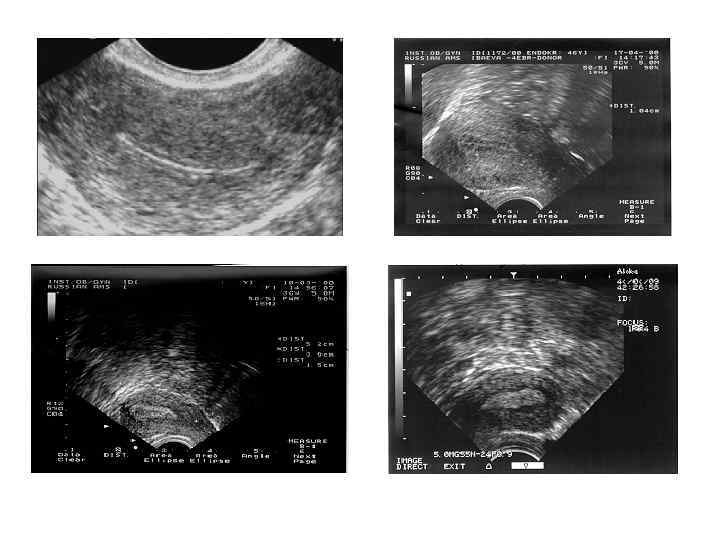

Визуализация яичника при ультразвуковом исследовании

Визуализация структуры яичников на протяжении менструального цикла